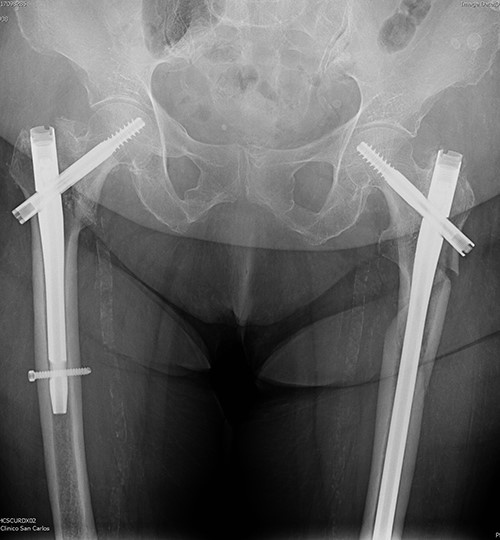

On examination, external rotation deformity of both lower limbs was evident, as well as pain upon palpation in the trochanteric region and during mobilization. The radiological study revealed a left and a right intertrochanteric femur fracture (Fig. 1). She was given analgesia, immobilized with two cutaneous tractions (Fig. 2), and was admitted to the Orthogeriatric Unit.

A. Anteroposterior pelvis radiograph evidencing a left subtrochanteric (AO:32-B2a) and a right intertrochanteric femur fracture (AO:31-A2.3). B. Radiograph of the right hip without any criteria of fracture instability. C. Radiograph of the left hip showing a simple wedge pattern of fracture.